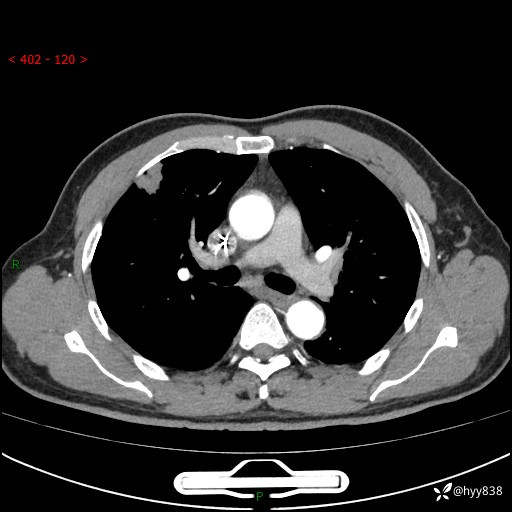

现病史:者10余天前因胸闷就诊于我院心血管内科,行胸部CT提示右肺上叶结节(24mm×16mm),考虑肿瘤性病变可能。无畏寒、发热、盗汗,无咳嗽咳痰,无咯血,无胸痛,无呼吸困难等不适,未予特殊处理。今为求进一步诊治,前来我院就诊,门诊以“肺结节待查”收住入院。 患者自起病来精神、食欲、睡眠尚可,体力下降,体重无明显变化。

胸部CT平扫+增强